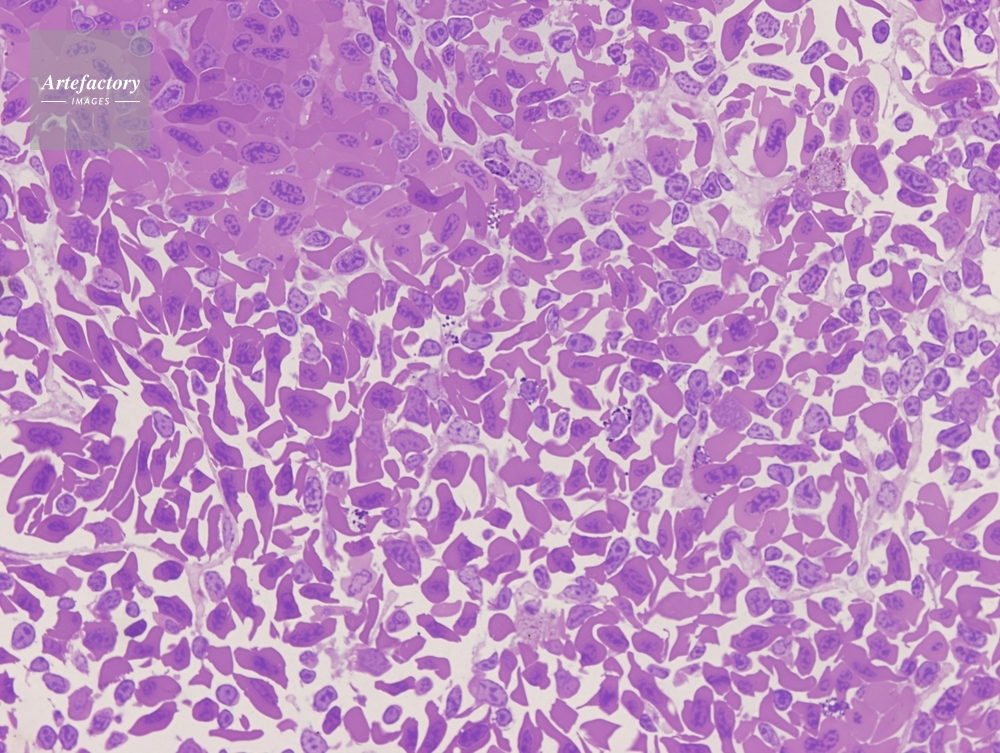

| 作品タイトル | イモリ 脾臓 | モデルリリース | なし | |

| 作家 | OLYMPUS CORPORATION Technolab | プロパティリリース | なし | |

| ソース | ピクセル数 | 3455px × 2602px | ||

| 撮影地 | 印刷サイズ | 20.3cm × 15.3cm | ||

| 撮影年月日 | 2007/4/20 | データサイズ | 4.8MByte | |